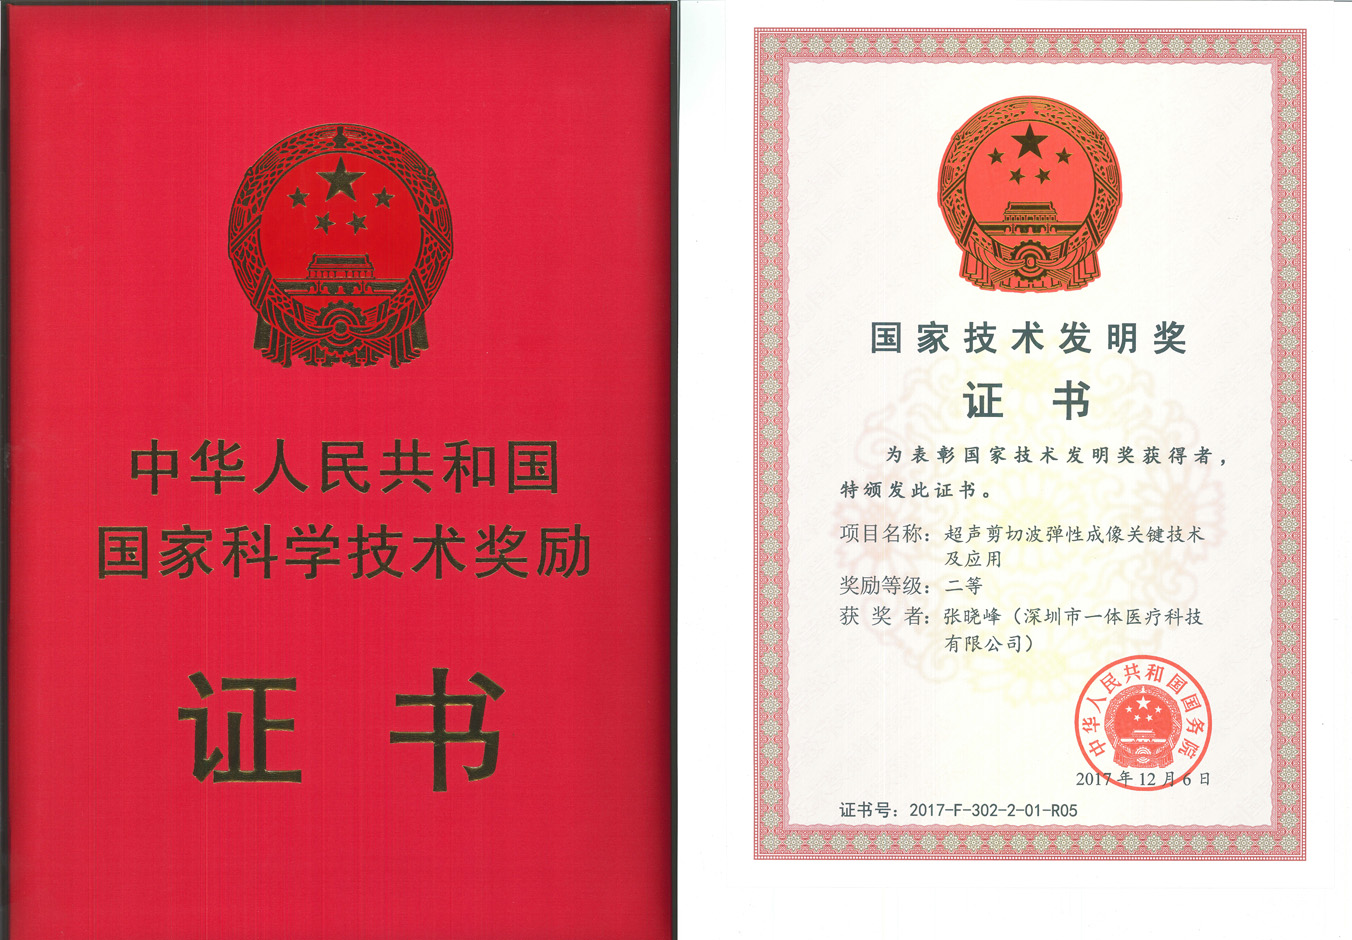

еӣҪ家жҠҖжңҜеҸ‘жҳҺдәҢзӯүеҘ–